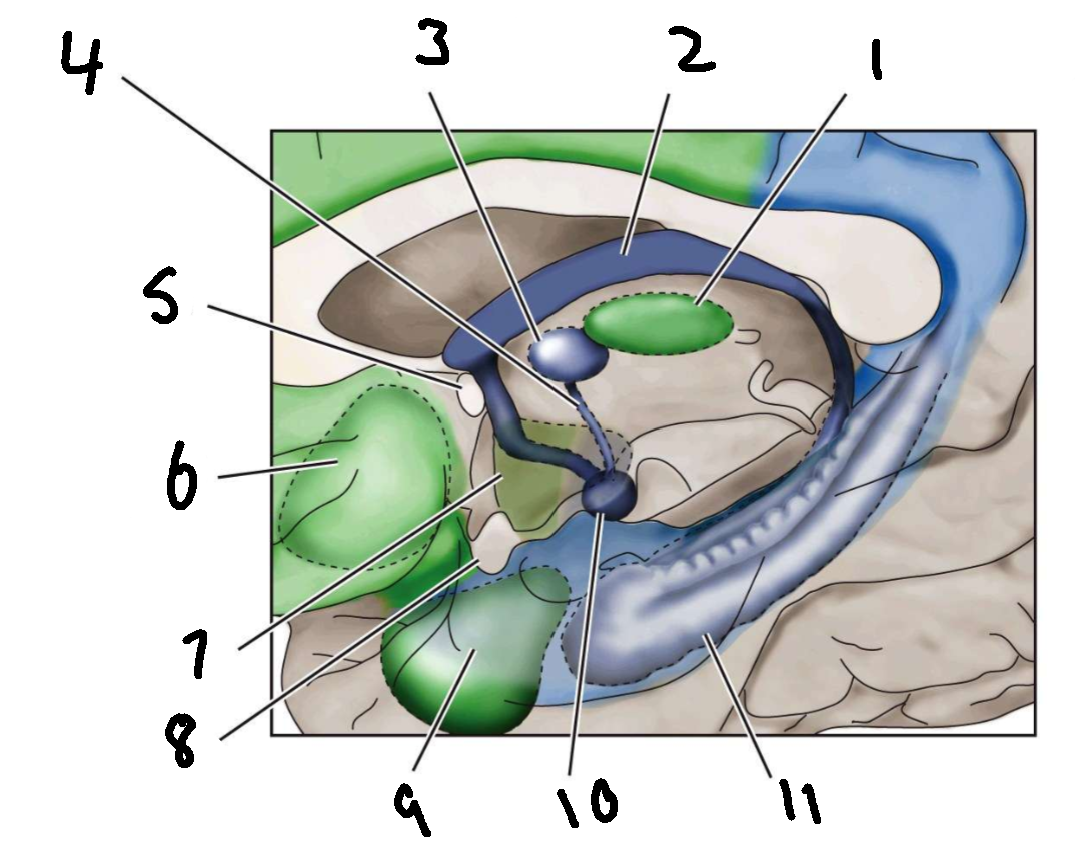

What is 1?

mediodorsal nucleus of the thalamus

What is 2?

fornix

What is 3?

anterior nucleus of the thalamus

What is 4?

mammillothalamic tract

What is 5?

anterior commissure

What is 6?

ventral basal ganglia

What is 7?

hypothalamus

What is 8?

optic chiasm

What is 9?

amygdala

What is 10?

mammillary body

What is 11?

hippocampus